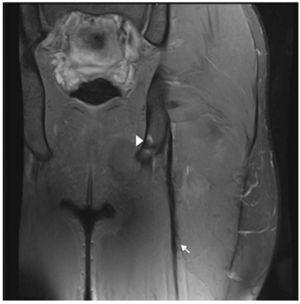

Un jugador de futbol professional de dinou anys patí un dolor sobtat a la regió posterior superior de la cuixa en esprintar que l’impedí jugar. Els senyals clínics mostraren una tibantor aguda dels isquiotibials (palpació dolorosa, rang de moviment [ROM] limitat, disminució de la força, estirament dolorós i dificultat per caminar normalment). Es practicà RM 24 hores després del traumatisme amb un escàner 3-T (Titan Vantage, Toshiba). La lesió i les característiques de CLBF es descriuen a les figures 1 i 2. El diagnòstic final fou una lesió proximal UMT de CLBF localitzada a 10 cm de la tuberositat isquial i a 6 cm des de l’inici d’UMT. El temps de baixa previst fou de 7-8 setmanes. El tractament de recuperació consistí bàsicament en 3 fases: fisioteràpia, entrenament de força i neuromuscular al gimnàs i entrenament individual específic de futbol al camp.

Figura 1 Les imatges coronal i axial en T2 amb supressió de greix de l’isquiotibial esquerre mostren trencament parcial de fibres a la UMT proximal de CLBF representades per una àrea d’alta intensitat de senyal adjacent a la UMT (fletxa). S’observa també ruptura d’algunes fibres del semitendinós (+). Ventre muscular semitendinós (ST), cap proximal del bíceps femoral llarg (long head biceps femoris [LHBF]), tendó semimembranós (punta de fletxa) i nervi ciàtic (*). En el tall coronal s’observa edema muscular de patró de ploma d’au.